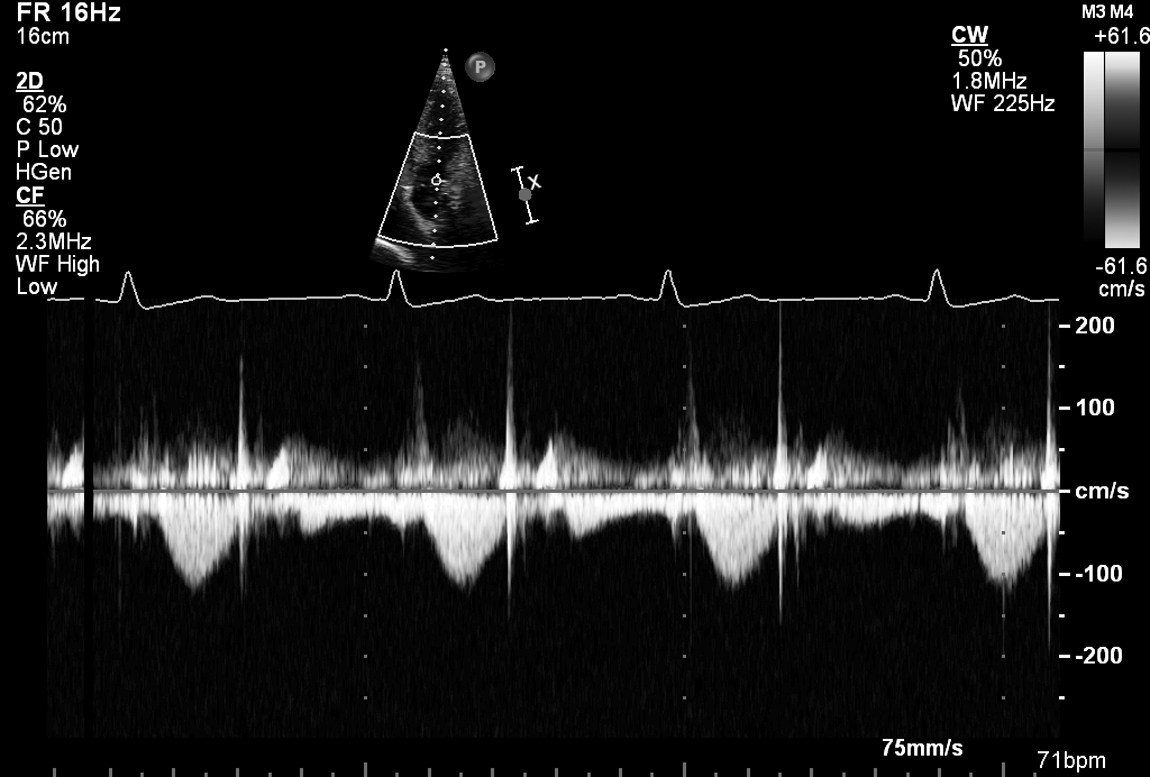

A 35-year-old woman presents with worsening exertional dyspnoea over 3 months following a viral illness. She has no chest pain. She is a non-smoker. ECG shows LBBB. The basal septum thickness is 0.5 cm and the LV is 6 cm at end-diastole. Peak LVOT velocity is 0.8 m/s and peak aortic velocity is 1.2 m/s. Her echo is shown in Fig 5.1, 5.2 and Videos 5.1, 5.2, 5.3, 5.4, 5.5, 5.6, 5.7, 5.8, 5.9, 5.10 and 5.11.